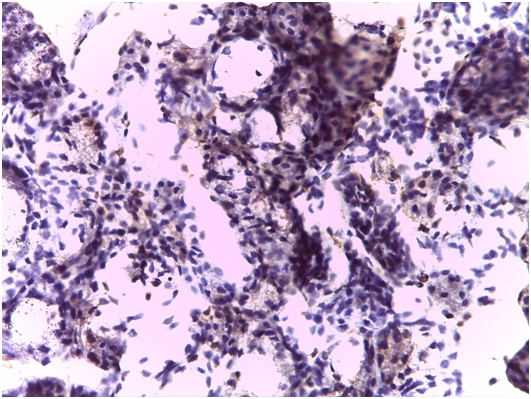

Figure 7 Expression of CD68 in the salivary glandular tissue (Original magnification 40x).

Immunohistochemical findings

As regards to immunohistochemistry (IHC), all cases of GBS have expressed focal positivity that ranged from moderate (++) to strong expression (++++) for CD68 (Figure 7) and CD16b (Figure 8). These cases have revealed a natively strong immunoreactivity for CD34 (Figure 9). The twelve cases showed negative expression for cathepsin-K. By contrast, the representative slides of both SS and normal mucosa did not display any significant immunoreactivity for the above mentioned immunohistochemical markers. To contrast, the main histological and immunohistological findings were compiled in Table 2.

Gilbert-Behçet syndrome characterizes no specific findings. The general histological pattern of neutrophilic infiltrations, lymphocyte aggregations of the surrounding vessels and vascular proliferations have been observed in biopsy specimens of oral apthae and genital ulcers. However, none of these is specific. Moreover, accumulation of lymphocytes, neutrophils, and eosinophils as well as edema and leukocytoclasia occur at the site of the pathergy test within the first 12 hours.16,17 Again, this may hold true at any non-specific inflammatory site. This study appreciate the conspicuous perivascular and periductal infiltrations of neutrophils and macrophages, the rich intervening vascularity and the dusty acini in GBS. The characteristic lymphocytic within the atrophic glandular parenchyma, acinar degeneration and proliferations of epimyoepithelial islands were substantially remarkable in all labial salivary gland specimens of SS. This highlights the diagnostic validity of this biopsy in diagnosing such rheumatic diseases. Immunohistochemically, the moderate to strong expression for CD68 implied the high propensity of macrophages aggregations on the normally appearing acini; possibly attacking some bacterial strands with streptococcus sanguinis highly suspected. Similarly, the moderate to strong expression expression for CD16b indexed an affininty of perivascular and periductal neutrophilic infiltration. Staining strongly for CD34 has marked the proliferative incidence of endothelial vessels and increased intervening vascularity which signifies the vascular pathognomonicity of GBC. The negative expression for cathepsin-K emphasizes the non-granulomatous content of both GBS and SS. Reviewing the literature, caveats of exacerbating GBS encompassed, quite correctly, uveitis, aneurysms and CNS responses of which recurrent uveitis was considered highly striking for liability of visual loss, especially in the left eye.18-20 This find goes hand in hand with the present study therein uveitis was commonly observed.